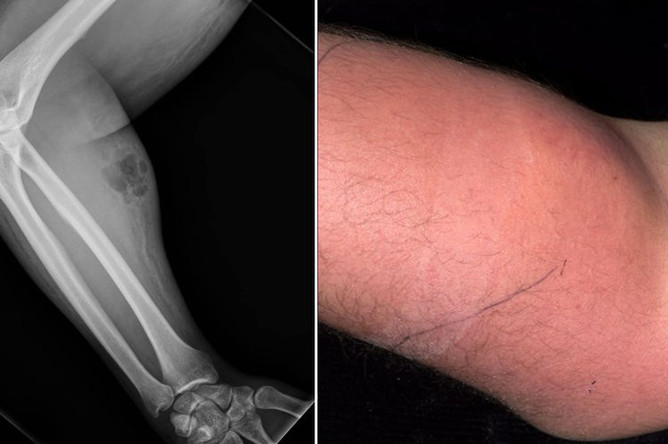

Сперма в вену: как не надо лечиться

Ирландец вводил себе в руку сперму, чтобы вылечиться от боли в спине

17.01.2019, 21:31